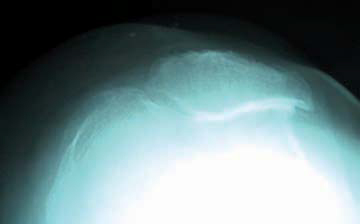

Pincement majeur ou subluxation, la difficulté est de trouver un petit espace entre la rotule et le fémur. Adapter l’inclinaison de l’aiguille en appréciant, sur les radiographies en incidence axiale, l’inclinaison de la facette rotulienne (fig. 3) pour glisser l’aiguille juste au bon endroit.